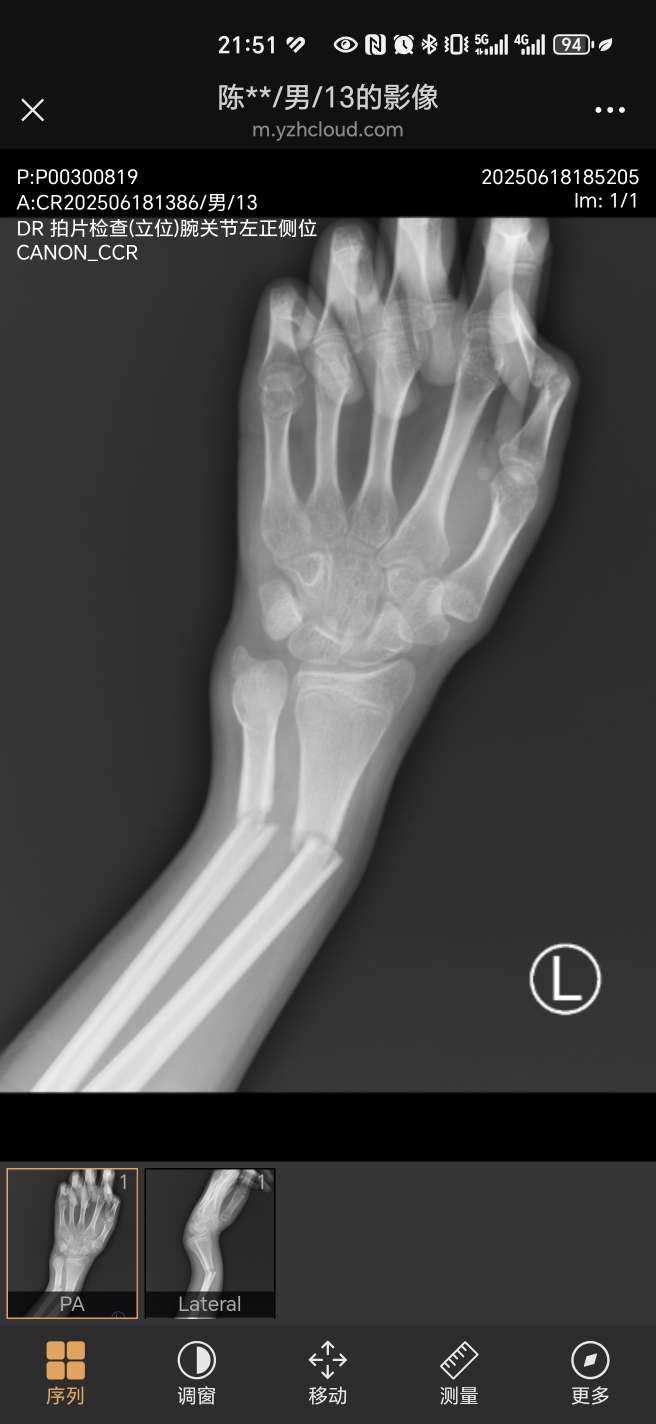

是的,刚才跟我说了,他这个要从手腕那个位置打一根钢钉,一直到肘部,再从肘部打一个钢钉直到手腕。[em1 ...

唉,是呀,真的是意外,慢慢骑,他新手,撞路灯杆摔倒了,手腕撑地,就这样了

这么严重,看着就心疼。我儿子在学校被他同学碰到,尺骨裂了一点缝,石膏固定了一下。30天好了。